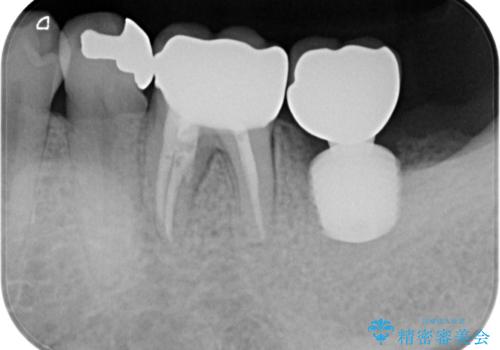

レントゲン写真より、一番奥の歯の根尖部に大きな病変(炎症により骨が溶けている状態)が認められたため、根管治療を行うこととしました。

根管治療後に痛みは一次消退しましたが、半年ほど経過しても病変は改善しておらず、歯根が破折している状態となっていました。